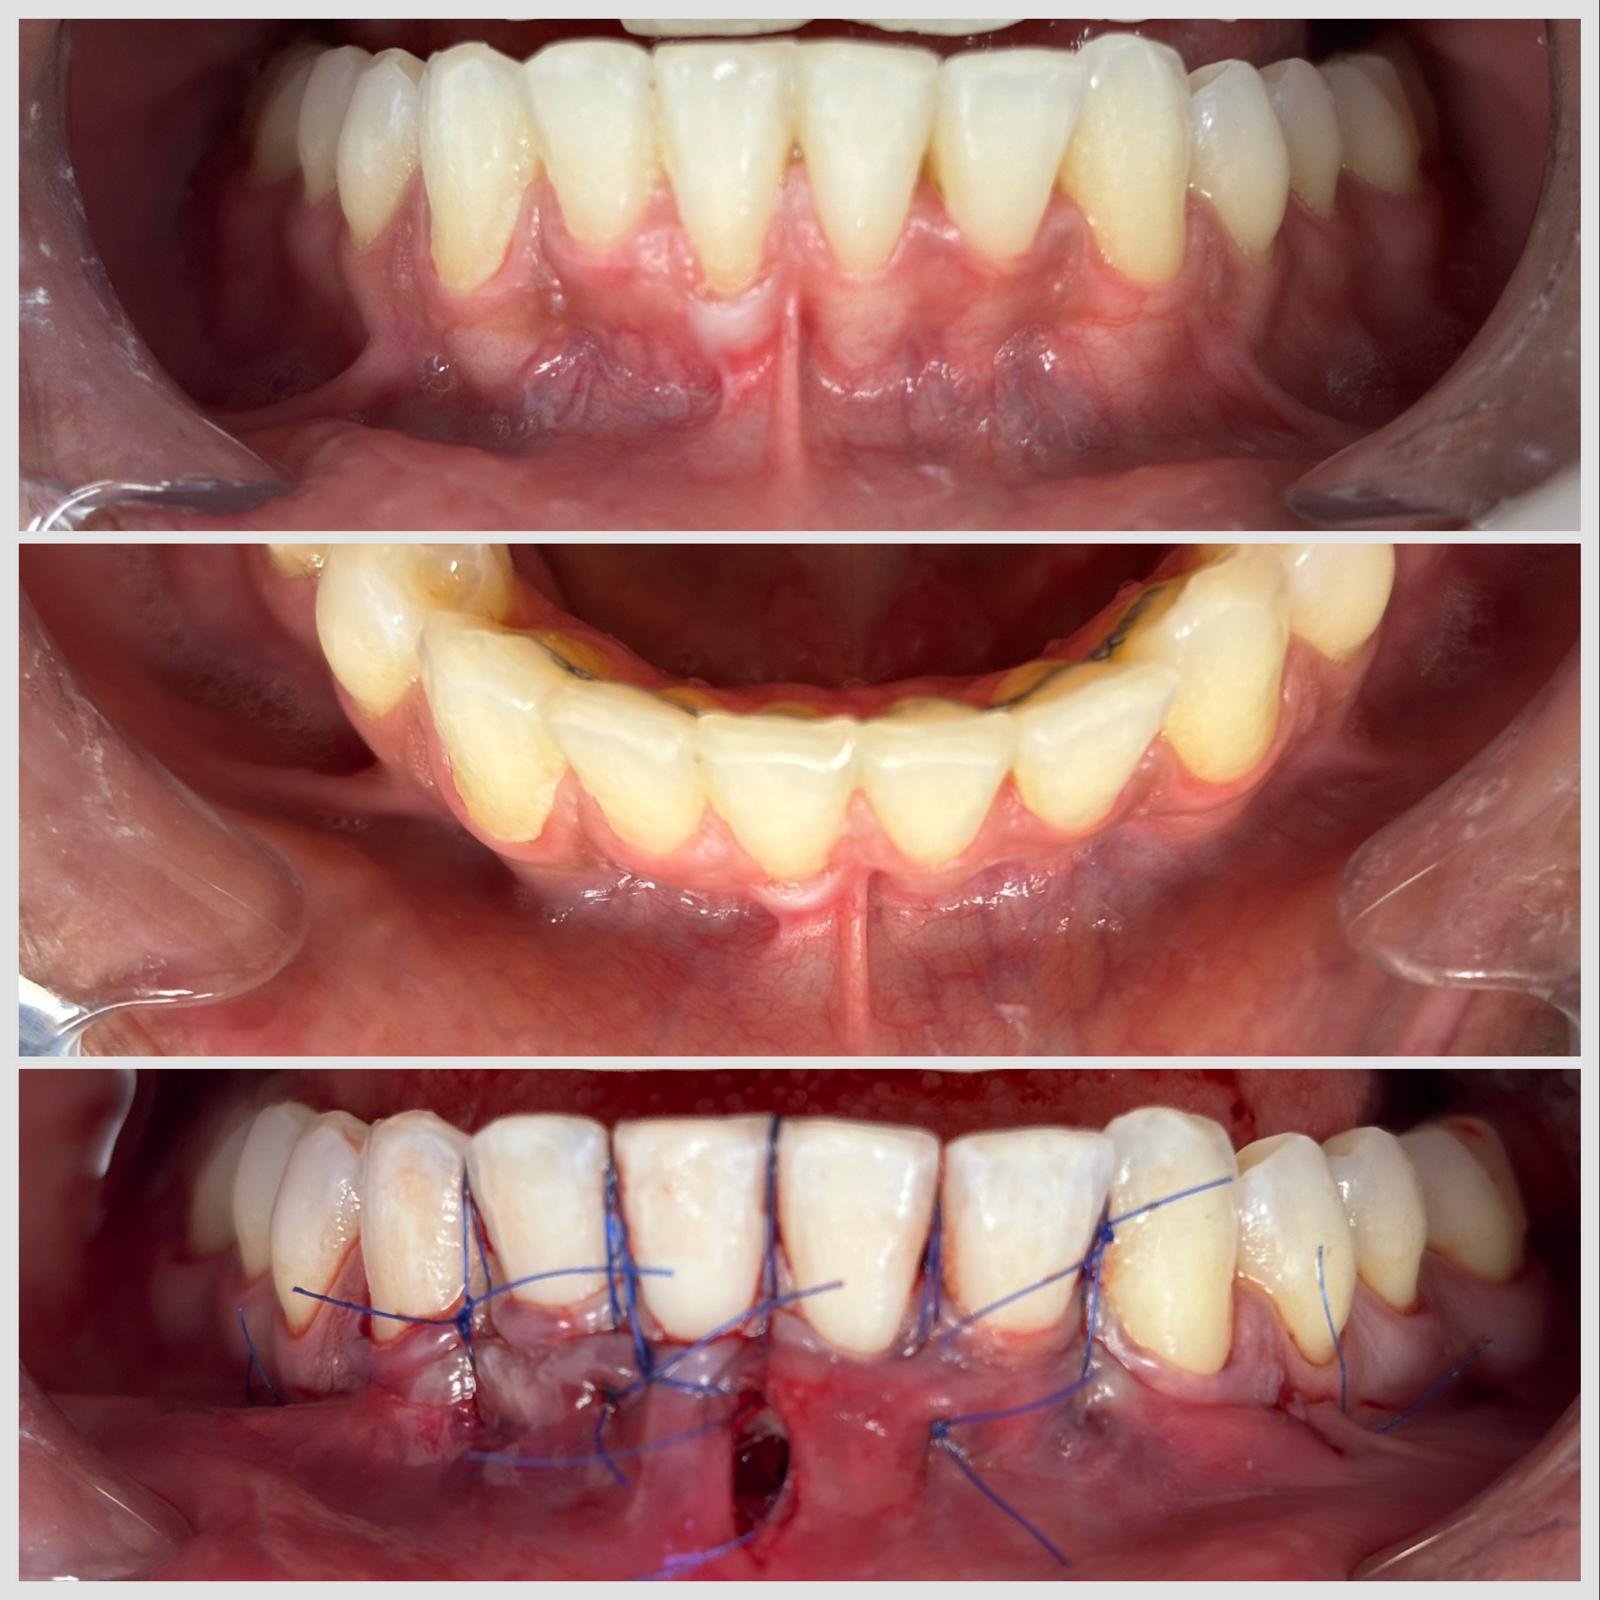

Greffe conjonctive réalisée par technique tunnelisée pour traiter une récession gingivale à Apolline Dental Care à Corbeil-Essonnes

Greffe Conjonctif

#parodontologie